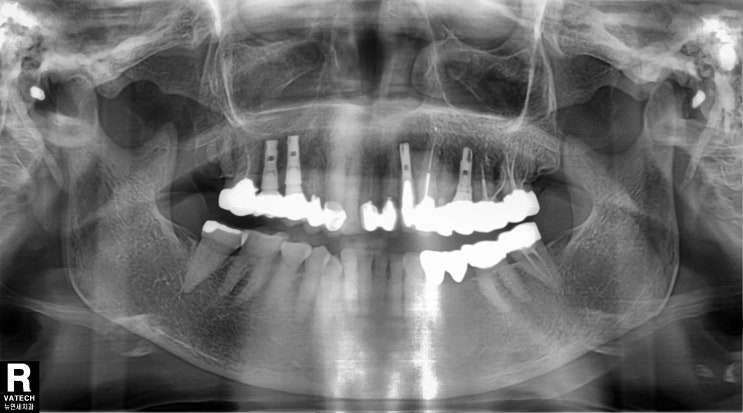

다른 치과에서 상악우측 제1대구치, 상악좌측제1소구치, 상악좌측제1대구치, 하악좌측 제2대구치, 하악좌측...

잇몸이 안좋아 상악좌측 제1대구치 및 제2대구치 모두 발치하고 임플란트 2개 하자는 진단을 받고 치아를 ...